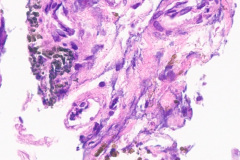

Biopsy/Pathology Diagnosis: Iron Pill Bronchitis

Initial diagnosis of IPA is not always readily distinguishable on cytology examination of slides. There may be a presence of a small amount of yellow-brown material on modified Romanowsky and Papanicolaou stains which without the clinical history of aspiration could easily be interpreted as non-specific artifact or other types of pigmented particles such as hemosiderin or carbonaceous particles.6 Histological examination of biopsy material is typically the gold standard for diagnosis, wherein iron pill injury is characterized by the presence of crystalline iron fibrils in the presence of necrosis or in an ulcer base.1 An iron stain such as Perls’ Prussian Blue can aid in determining the iron composition of the yellow-brown material by staining iron as a bright blue color.9 Microscopic features of the biological response to the aspiration exposure may include the presence of multinucleated giant cells, hemosiderin-laden macrophages, granulomas, and reactive atypia of squamous metaplasia. Care should be taken when assessing the Prussian Blue stain results as the hemosiderin in macrophages will also stain positively.9